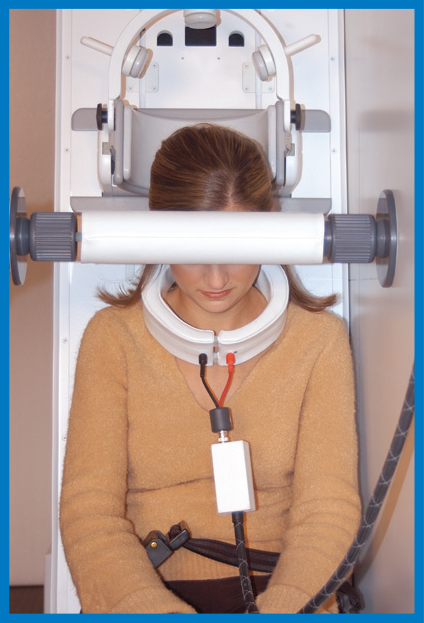

Cervical FlexionCervical Extension

Cervical FlexionCervical Extension

The Upright MRI can provide diagnostic pictures of the neck (cervical spine), the lower back (the lumbar spine), and the joints of the body over their full range of motion. Flexion and extension views of the spine, for example, often provide critical information that doctors need in order to achieve the best results for their patients. No other MRI scanner can do this.